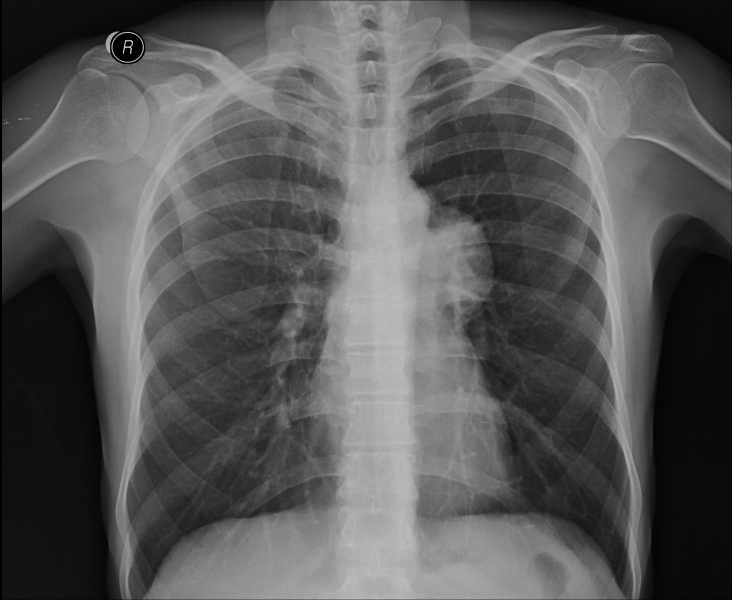

Chest Xray